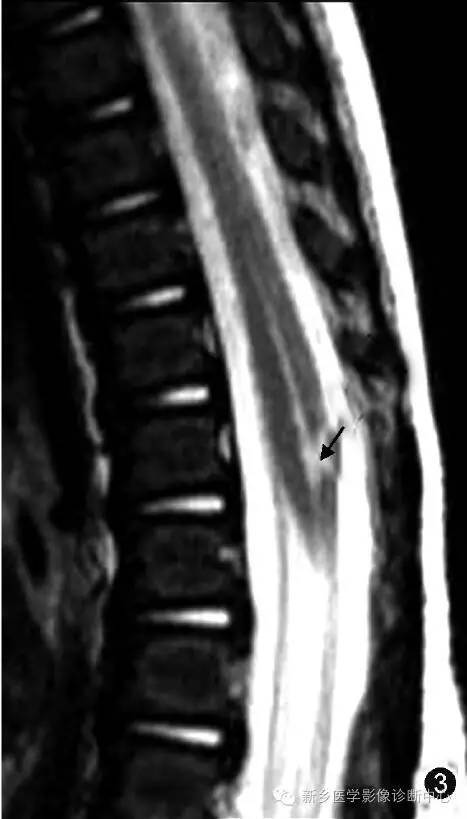

超声是诊断胎儿或新生儿第五脑室的一种常用检查方法[12](图1~3) 。 第五脑室在超声矢状切面图上显示为脊髓圆锥区域囊状扩张的低回声区并可与中央管相通 , 在超声横断切面图上表现为扩张的低回声囊腔且与周围脊髓组织有着较为清楚的分界 。 MR检查为诊断第五脑室的主要手段 。 第五脑室在MRI上通常表现为脊髓圆锥内边缘清楚的卵圆形囊腔 , 形态规则 , 囊壁光整 , 且与周围正常的脊髓组织分界清楚 , 囊内为T1WI低(图4 , 5)、T2WI(图6 , 7)高的脑脊液信号 , 囊内分隔及囊周水肿性改变比较少见 , 增强扫描后囊壁不强化 。 第五脑室需要与位于脊髓圆锥的囊性肿瘤如室管膜瘤、星形细胞瘤以及脓肿相鉴别 , 囊性肿瘤和脓肿的囊壁通常有不同程度的强化 。 脊髓圆锥的转移瘤很少见 , MRI表现通常为肿瘤强化且周围伴有明显水肿[13] 。 脊髓背侧的严重损伤也可发展为囊性病灶 , 但目前报道的大多数第五脑室病例并无外伤病史[6] 。 脊髓内的表皮样囊肿和皮样囊肿由于成分复杂导致MRI表现多变[14] , 而第五脑室的MRI表现单一 。

图1~3 男 , 5 d 。 超声矢状切面显示第五脑室是位于脊髓圆锥内且囊壁光滑的囊腔(图1,);

图2为图1的示意图;矢状面T2WI显示第五脑室是位于脊髓圆锥中央的囊性扩张结构 , 囊内呈高信号(图3 , )